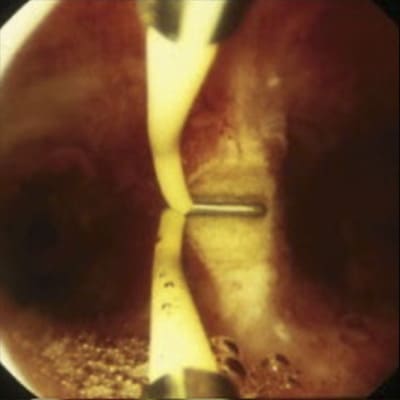

Tabique uterino